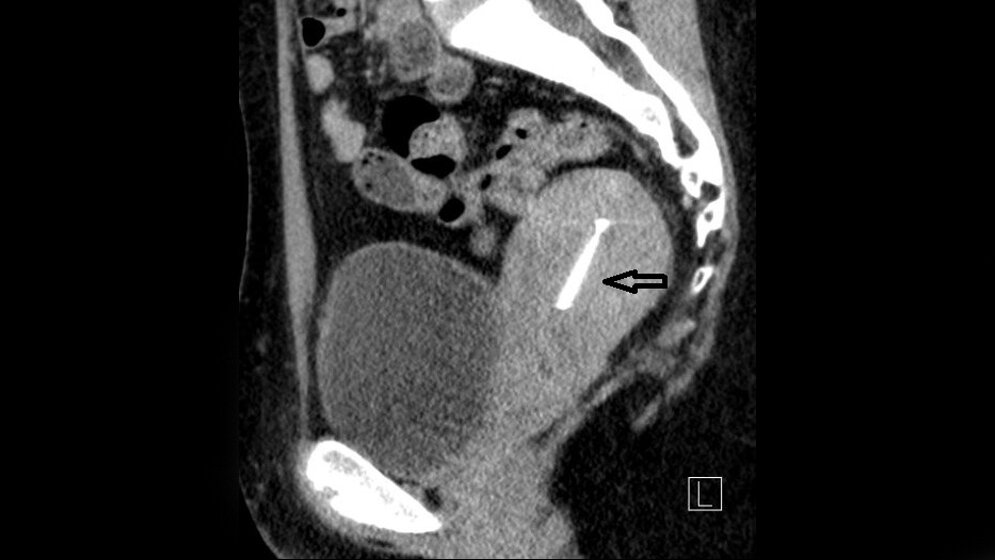

Die Retroflexion ist oft mit der Retroversion des Uterus kombiniert, die Dextroposition häufig bei Frauen mit Anteversion und die Sinistropositio mit Retroversion kombiniert.

Schlüsselwörter: CT, MRT, Becken, Uterus, Retroflexio

Retroflexion is often combined with retroversion of the uterus and lateroversion to the right was seen in women with anteversion, whereas the opposite trend was observed with the retroverted uterus.

Keywords: CT, MRI, pelvis, uterus, retroflexio